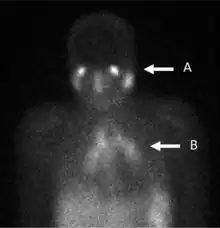

Gallium scan showing panda (A) and lambda (B) patterns, considered specific for sarcoidosis in the absence of histological confirmation